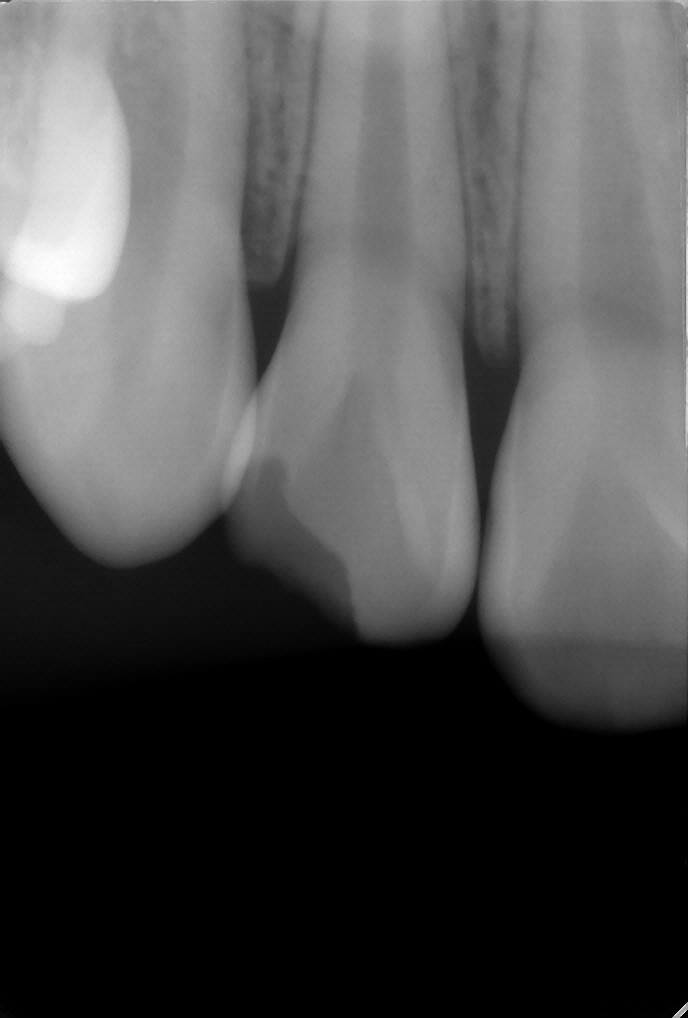

12歳女の子:外傷で欠けた前歯をダイレクトでボンディング修復

外傷による歯冠破折

12歳・女の子 ぶつけて前歯欠けた

1回

デンタルエックス線にて歯根破折がないことを確認し、ダイレクトボンディングにより形態修復を行なった。

55000円

変色、破折